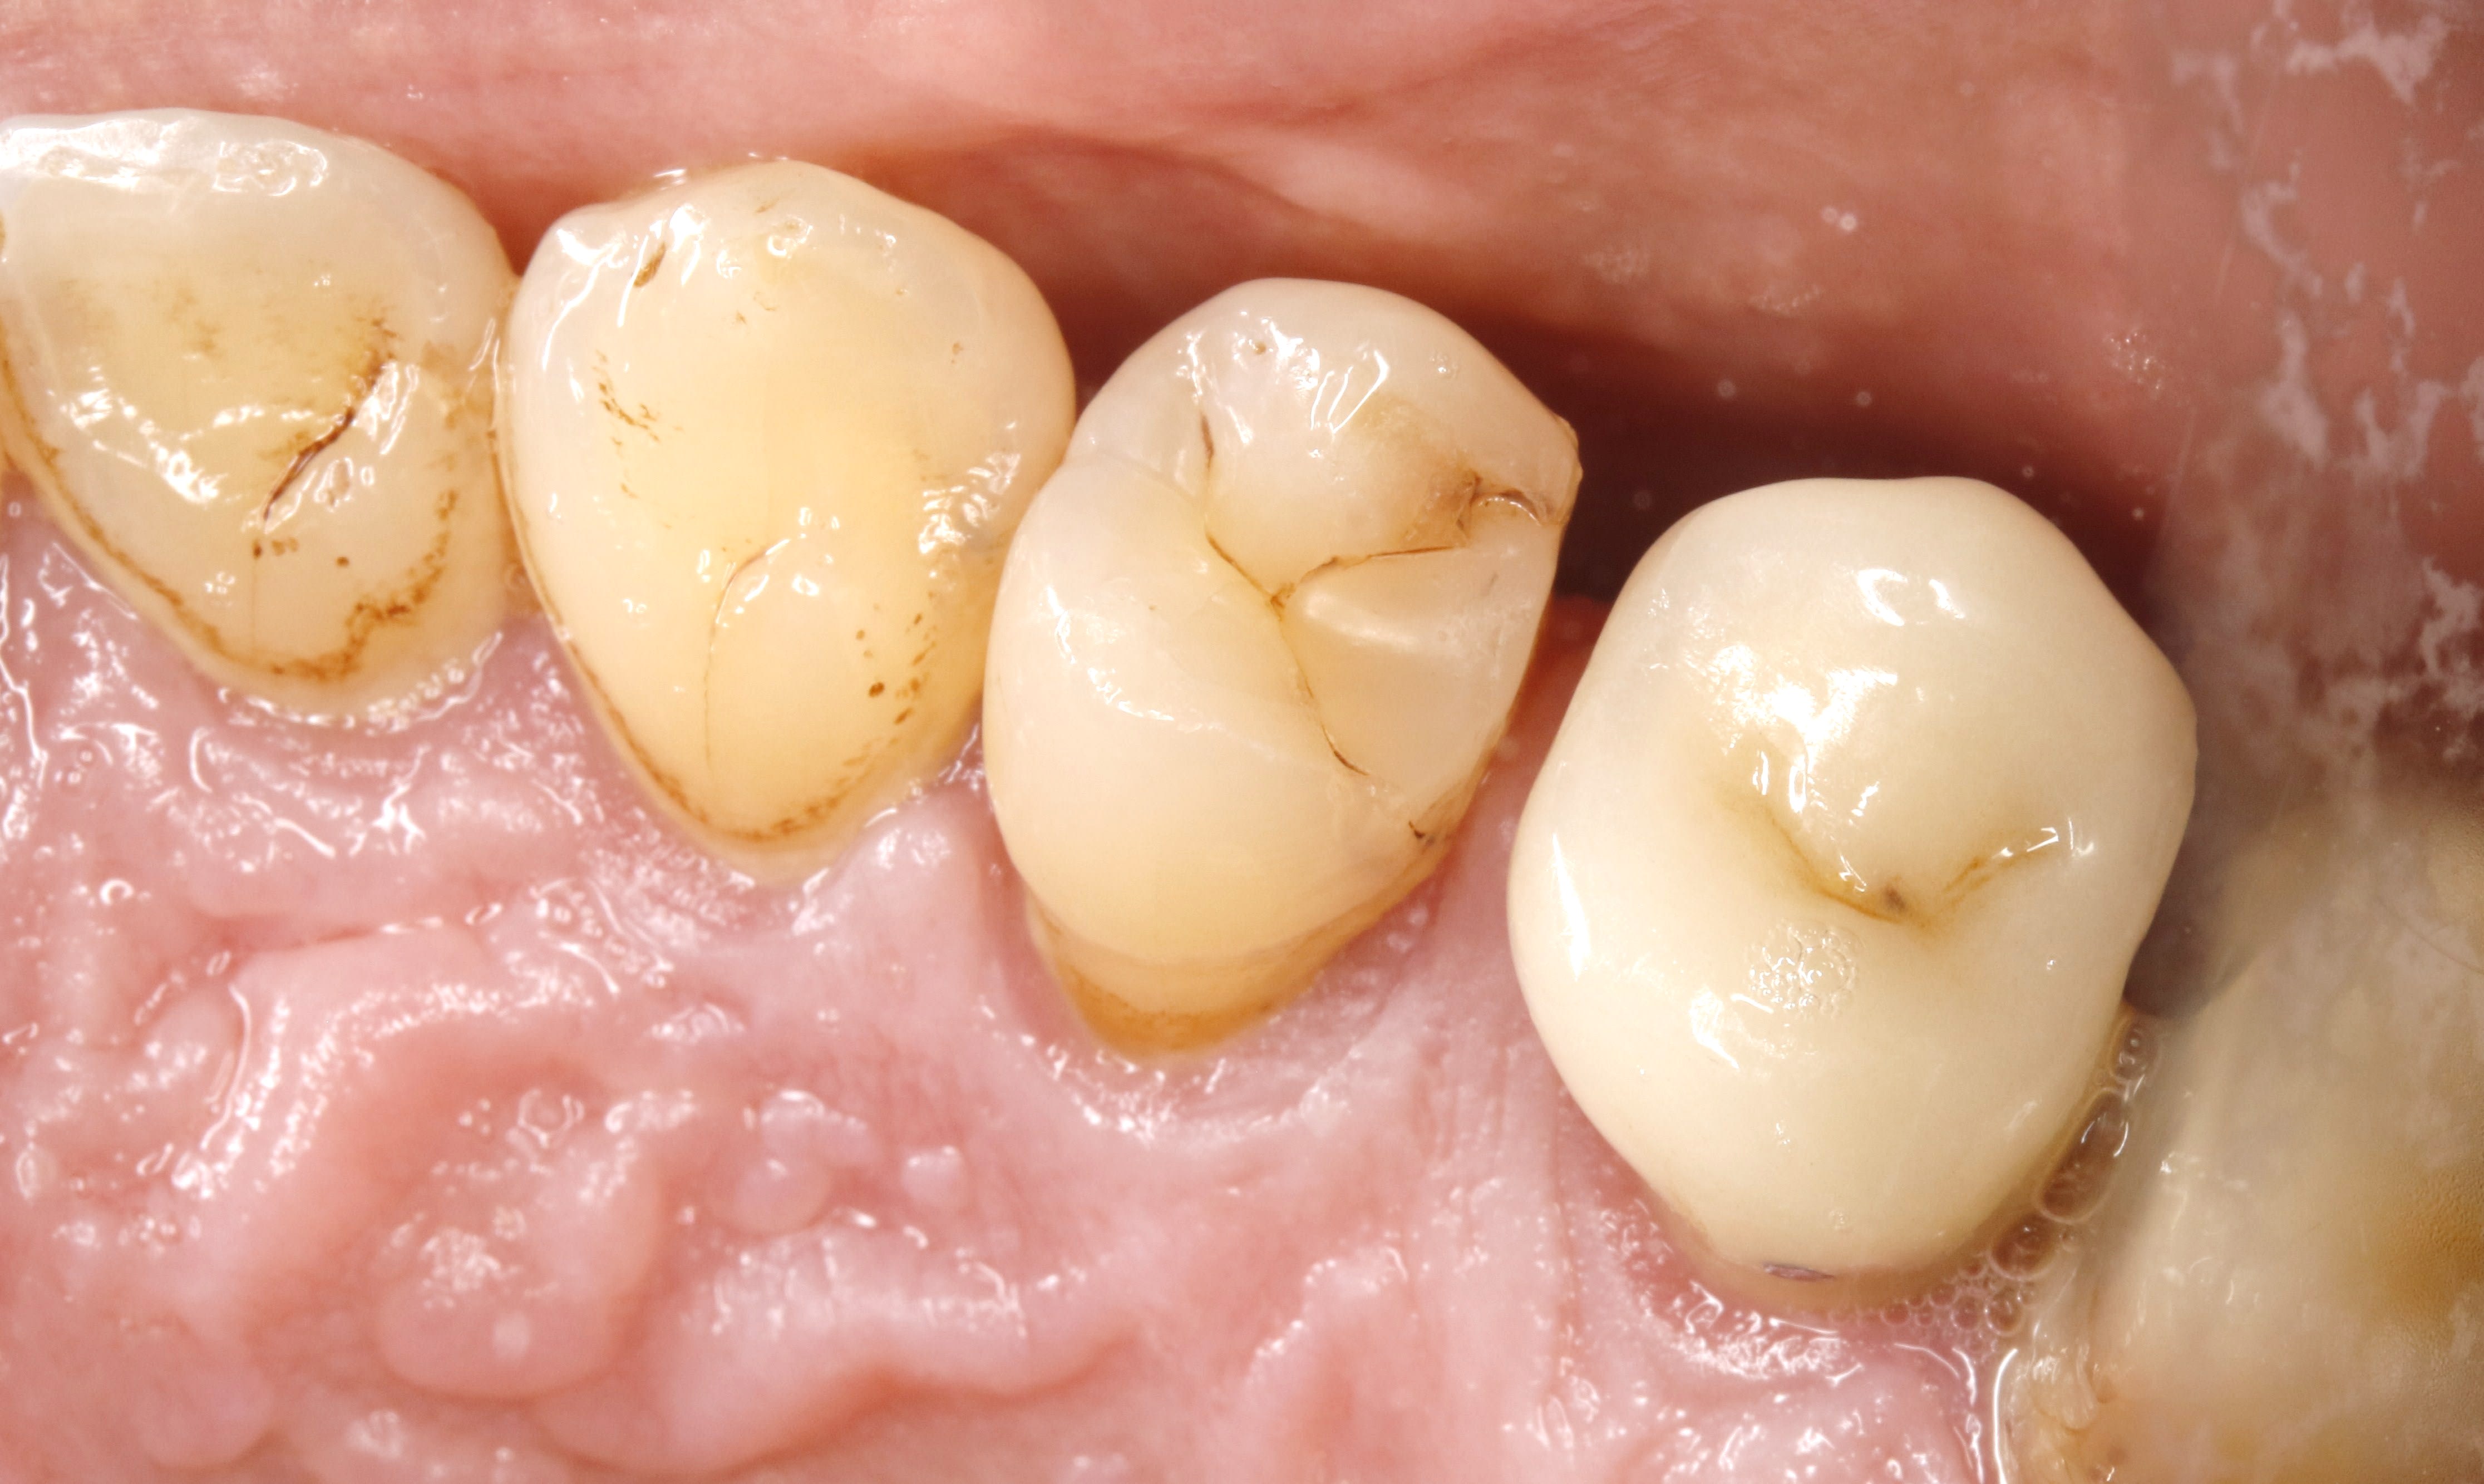

et donc je cherche en bas secteur 30 . et voilà . j avais pas vu , ou tout au moins je manquais encore de conviction quand au décalage des crêtes marginales .

tu vois la crête mesiale de 6 en fer ? avec la mega facette d usure en proximal ?

et bien au fur et a mesure des usures dentaires , le metal lui ne s est pas usé , et ça a créé une prématurité .

or une prema sur une crête , ç est un drame pour le mvt OIM / ORC .

donc avant toute chose et avant de reprendre le cas , hop , il faut remettre à niveau la crete marginale à la fraise . et voilà . à partir de là on peut recommencer a bosser .

Cc q2y3u4 - Eugenol